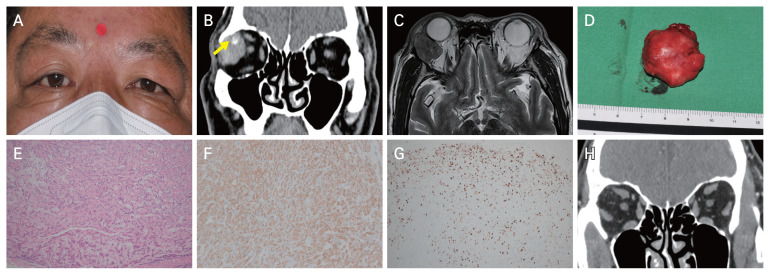

Lacrimal Gland Myoepithelial Carcinoma Managed with Surgical Excision and Radiation: A Case Report.